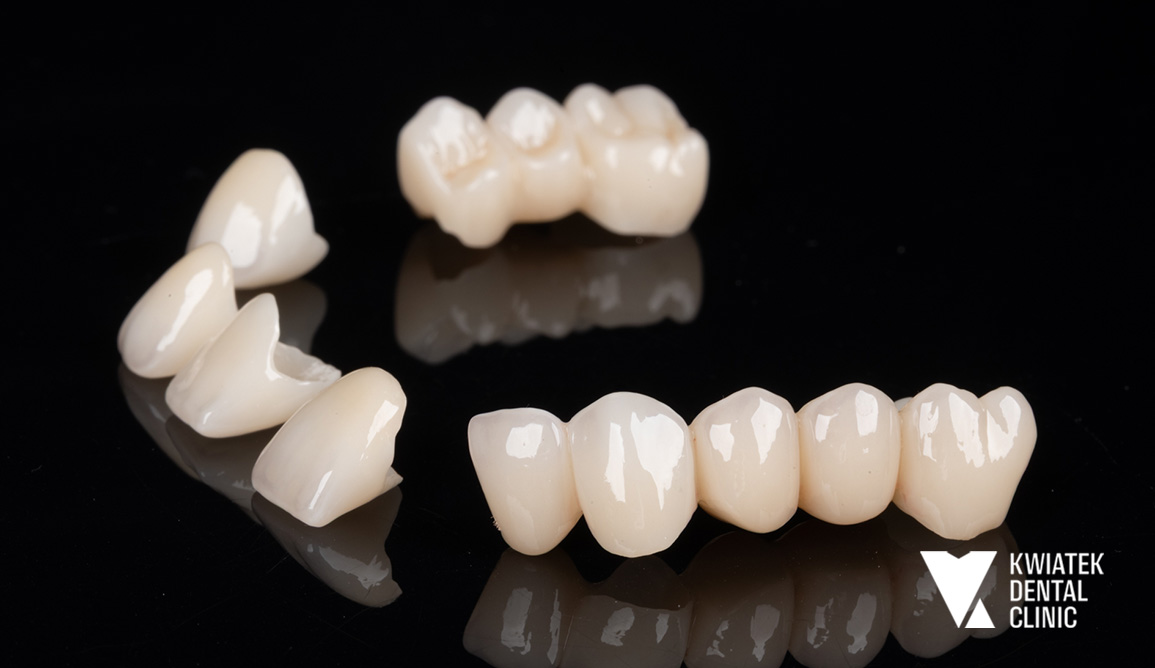

Kolejnym ważnym etapem była odbudowa brakujących zębów w odcinku bocznym żuchwy. Wykonano zabieg implantacji w pozycjach zębów 36 i 47 z użyciem systemu implantologicznego MIS C1 oraz z zastosowaniem szablonu chirurgicznego i nawigacji implantologicznej. Po zakończeniu procesu osteointegracji wykonano odbudowy protetyczne na implantach oraz korony protetyczne na zębach własnych Pacjentki. Równolegle przeprowadzono estetyczną rekonstrukcję zębów dolnych metodą flow injection, która pozwoliła na odbudowę ich kształtu i przywrócenie prawidłowych proporcji uśmiechu. Całość leczenia uzupełniono zabiegiem wybielania zębów metodą gabinetową z zastosowaniem systemu Philips Zoom.